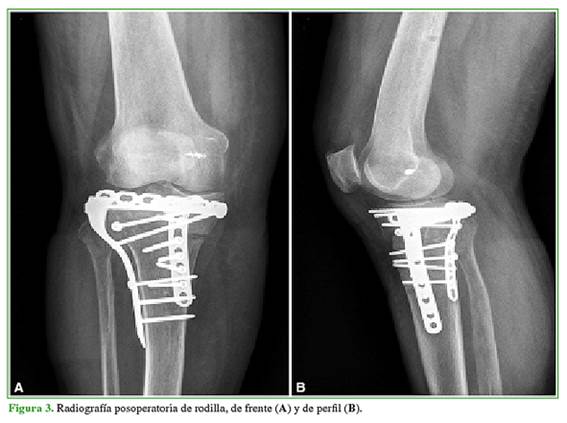

Posteriormente se retira el realce y se reposiciona a la paciente en decúbito dorsal estricto. Se coloca un distractor femoral en función de distracción en varo del platillo tibial externo para luego proceder al abordaje anterolateral que se extiende desde el aspecto posterior del cóndilo lateral, dirigiéndose a un punto localizado a dos traveses de dedo hacia lateral de la cresta tibial, distal a la tuberosidad anterior de la tibia. La incisión debe estar centrada entre la cabeza del peroné y el tubérculo de Gerdy. Los dos tercios distales de esta incisión suelen ser suficientes para el abordaje, aunque si es necesario, puede extenderse a proximal. Si se lleva a cabo una técnica mínimamente invasiva, se selecciona el tercio medio de esta incisión. Luego de atravesar el tejido celular subcutáneo, se identifica la banda iliotibial y se incide siguiendo la orientación de sus fibras. Por debajo se encuentra el músculo tibial anterior, que se desinserta en su porción proximal y anterior para darle lugar a la osteosíntesis. Por último, se realiza una capsulotomía transversal distal al menisco lateral para visualizar la reducción articular adquirida. Se reduce la fractura otorgando contención mediante un injerto óseo autólogo tricortical de cresta ilíaca. Se realizan la reducción directa y la estabilización con una placa bloqueada regional de tibia proximal de 5 orificios y 3,5 mm (Figura 3).

Por último, ante la inestabilidad varo-valgo, se reconstruye el ligamento colateral medial con un arpón de 4,5 mm y se corrobora la buena estabilidad clínica y radiológica posterior. Se efectúa un lavado profuso de las heridas con solución fisiológica y se cierra por planos en forma convencional con puntos separados. La tomografía del posoperatorio mostró una adecuada reducción de la fractura (Figura 4).